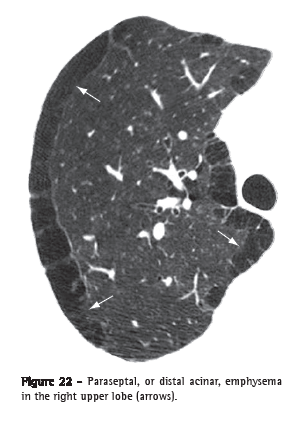

Paraseptal, or distal acinar, emphysema (enfisema parasseptal/acinar distal)

Paraseptal emphysema affects predominantly the distal alveoli and their ducts and sacs. It is characteristically delimited by any pleural surface or interlobular septa. On CT scans, it is characterized by areas of low attenuation in the subpleural and peribronchovascular regions, separated by intact interlobular septum (Figure 22).(37,38) It is sometimes associated with bullae.